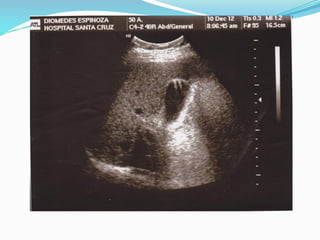

IMÁGENES ANECOICAS O ANECOGENICAS

Se producen cuando el haz de ultrasonido atraviesa un medio sin interfase

reflectante en su interior.

Suelen ser de este tipo las Lesiones Ocupantes de Espacio (LOES),

totalmente líquidas como los quistes, que además tienen el Artefacto

denominado Refuerzo Acústico Posterior, la parte blanca como cola,

después de la imagen negra